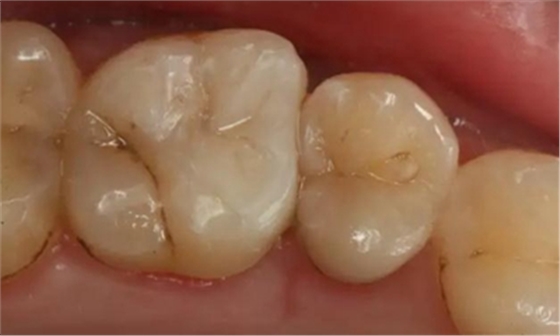

最后附幾例一次性根管治療+冠延長手術(shù)+高嵌體修復(fù)的病例,均為兩次完成。第一次就診:根管治療一次完成,后冠延長手術(shù),然后高嵌體預(yù)備,取模,第二次就診,拆線,試戴嵌體。具體在此不做詳細(xì)說明,圖中有詳解。

另外一個病例

病例3

該病例后期樹脂嵌體完成,為學(xué)生完成。沒有完成后的樹脂嵌體照片。病例已經(jīng)完成。